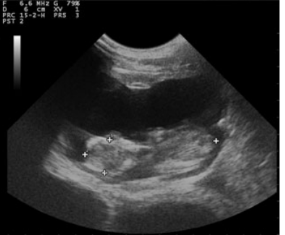

羊用B超机对冠臀长(CRL)测量定

冠臀长通常被认为是可靠的脚气测定法中的参数。测量应为从牙冠(头骨的***上部)取到的臀部(结束的ac骨)(图1和2)什么时候的胎儿完全伸展。GA和CRL之间的高度相关性在不同品种的***个和第三个中期。CRL是确定GA的可靠参数(r=0.99)早怀孕。得出了一个新公式,发现是确定GA的方法非常准确:y=24:42+0:39X其中Y=胎龄,X=CRL。但是,无法执行此测量随着怀孕的进行准确;较低的错误高山山羊胎儿有相关系数的报道在妊娠第33天至146天之间。

图1胎儿上冠状臀围长度的超声图像妊娠40天